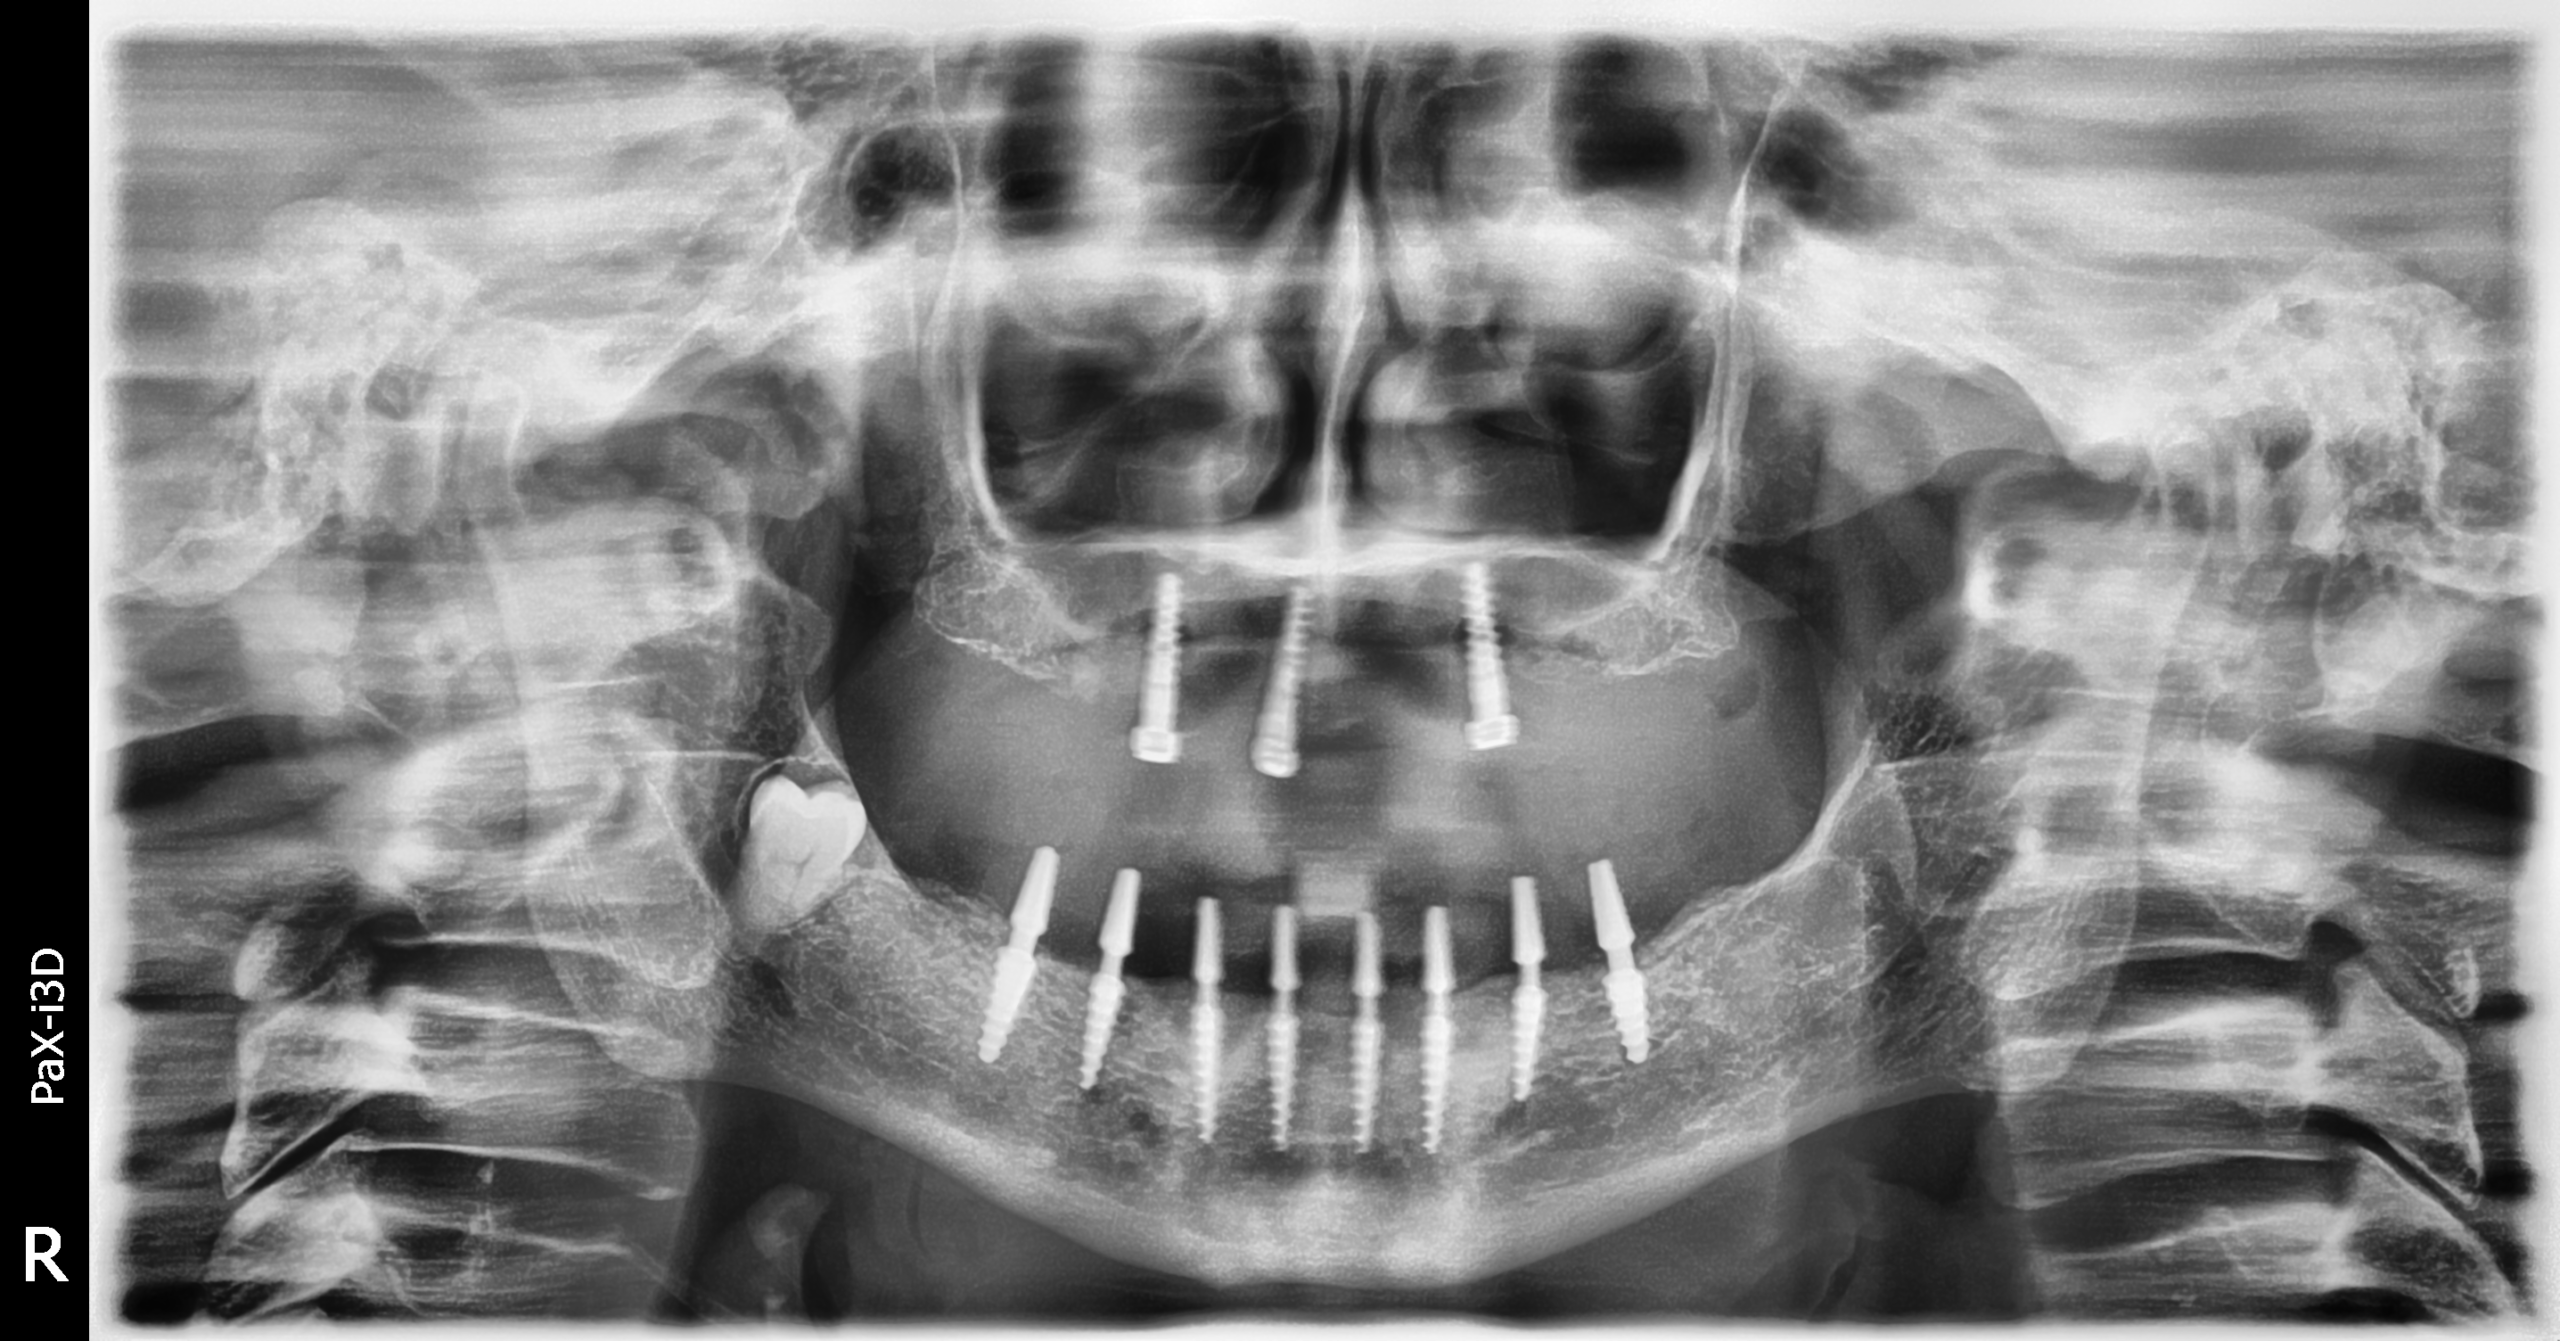

Implantes SLD-c

Secuencia de imágenes RX, antes y después de la inserción de implantes SLD-c en la parte inferior de la boca.

Paciente mujer de 65 años.

- Radiografía previa a la operación.

- Colocación implantes Radhex SLD-c parte inferior.

- Colocación implantes Radhex SLD-c parte inferior con soldadura.